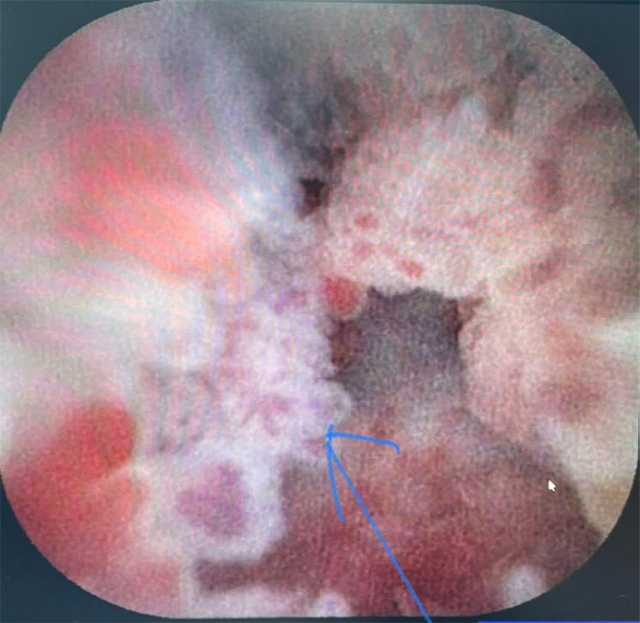

完全经自然腔道的胆囊内内镜光学成像发现胆囊管癌(箭头)

完全经自然腔道的胆囊内光学成像发现胆囊内的癌前病变(箭头)

该检查属于完全经自然腔道的超微创手术,即十二指肠镜下超细内镜和胆道内超声探头经口腔→食管→胃→十二指肠→胆总管→胆囊等人体自然腔道到达胆囊和胆管内,进行光学直视诊断和超声诊断。最终,患者明确诊断为早期胆囊管腺癌、胆囊颈体部息肉(癌前病变)、胆总管及肝内胆管无异常,纠正了之前其它影像报告的错误诊断。